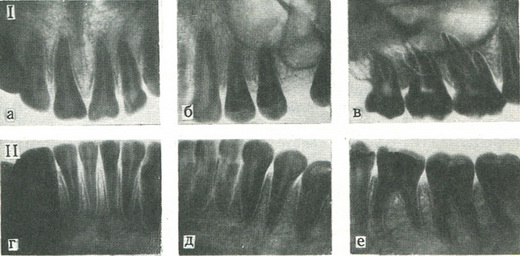

216. Рентгенограми постійних зубів.

I - зуби верхньої щелепи: а - різці; б - ікла; і премоляри; в - моляри; II - зуби нижньої щелепи: р - різці; д - ікла і премоляри; е - моляри.

На знімку верхніх центральних різців видно передній відділ носової порожнини, тінь носової перегородки і передньої носової ості (рис. 216). Між корінням центральних різців або вище їх вимальовується овальне або округле резцовое отвір. Коронка у центральних різців лопатообразная, більш широка, ніж у бічних різців. Назовні від бокового різця видно ікло, має трикутну списоподібну коронку і більш довгий корінь, ніж інші зуби.

На знімку малих корінних зубів верхньої щелепи є суцільна тіньова картина. При уважному розгляді знімка можна розрізнити дно верхньощелепної пазухи, зовнішню стінку носа і край виличної кістки. Малі корінні зуби мають два горба на жувальній поверхні. У першого малого корінного зуба два кореня (щічні і піднебінний), у другого - один. На знімку великих корінних зубів верхньої щелепи також визначаються дно верхньощелепної пазухи і вилична кістка, а за останнім великим корінним зубом виявляється тінь верхньощелепного горба. У великих корінних зубів є широкі коронки з кількома жувальними горбами; у перших двох великих корінних зубів є по три кореня - два щічних (медіальний і дистальний) і піднебінний; останній на знімку представляється більш довгим внаслідок проекційного спотворення.

На знімках зубів нижньої щелепи відзначається порівняно мало деталей в області різців - тінь підборідного горба в області малих корінних зубів і підборіддя отвір. Бічні різці ширші центральних; ікло має списоподібну коронку і найбільш довгий корінь.

У малих корінних зубів видно два жувальних горба. Нижні великі корінні зуби мають великі коронки з кількома жувальними горбами, медіальними і дистальными корінням. Нижче коренів вимальовується у вигляді просвітлення нижньощелепний канал. Уражені зуби відзначаються за загальноприйнятою формулою.